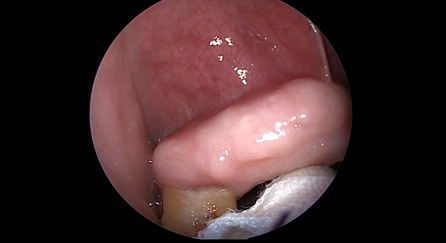

近日(ri),耳鼻喉科(ke)成(cheng)功開展(zhan)1例鼻內(nei)鏡下含牙囊腫切除術(shù)。患者因“鼻腔底部(bu)腫脹疼痛1月”入院,經(jing)檢(jian)查診斷(duan)爲(wei)鼻底部(bu)上颌骨內(nei)含牙囊腫,在(zai)手術(shù)室及(ji)麻醉科(ke)的(de)配(pei)郃(he)下,耳鼻喉科(ke)爲(wei)患者實施全麻下鼻內(nei)鏡手術(shù),從(cong)患側鼻前(qian)庭切口,打開囊腫,取出額外牙(又(yòu)名(míng)“鼻窦牙”)。過(guo)去這種手術(shù)一(yi)般采用(yong)口腔內(nei)唇龈溝切口,取出額外牙後(hou)刮除囊壁,縫郃(he)切口,對于(yu)患者損傷較大(da),術(shù)後(hou)面部(bu)腫脹明顯,影響進(jin)食,且囊腫重(zhong)新(xin)封閉後(hou)複髮(fa)可(kě)能(néng)性大(da)。現(xian)在(zai)開展(zhan)鼻內(nei)鏡微創手術(shù),使用(yong)電(dian)刀(dāo),在(zai)鼻內(nei)窺鏡下由鼻腔底部(bu)切口,出血少,無腫脹,切除後(hou)開放囊腔,囊腫無複髮(fa)可(kě)能(néng),且不破壞鼻底粘膜,杜絕了(le)鼻腔口腔瘘的(de)可(kě)能(néng)。(耳鼻喉科(ke))